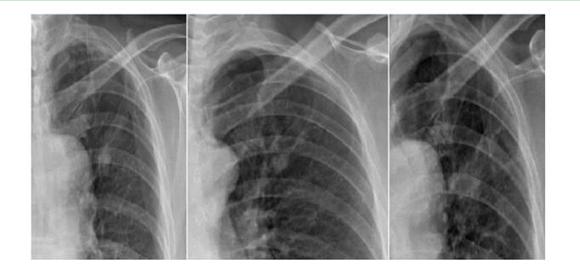

案例一:

第一年 第二年 第三年

案例解析:

在該案例中,病患在單一胸片檢查中,診斷出左上肺高密度結(jié)節(jié)影,前兩次在胸片攝影檢查得出的診斷結(jié)果并無(wú)大礙。相隔一年再去復(fù)查被誤診為“結(jié)核硬結(jié)灶”,并針對(duì)此而治療。但是,到了第三年之后,再次診斷發(fā)現(xiàn)結(jié)節(jié)影明顯增大,后才被確診為是肺癌,但為時(shí)已晚;如使用具備可視化點(diǎn)片功能的DR設(shè)備,胸片與胸透無(wú)縫結(jié)合,在透視下對(duì)“高密度結(jié)節(jié)影”全方位、多角度的高清點(diǎn)片獲取更多的確診信息,進(jìn)一步病理分析,第一時(shí)間得出確診結(jié)果,做到早發(fā)現(xiàn)、早治療,結(jié)果將會(huì)截然不同。